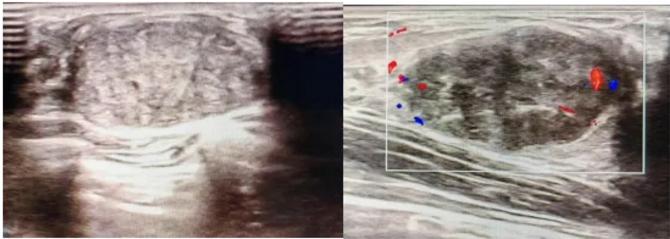

三、彩超檢查:無創(chuàng)檢查的“黃金眼”

高分辨率:可清晰顯示腫塊形態(tài)、血流信號(hào),敏感度達(dá)80%-90%。

2.彩超報(bào)告關(guān)鍵指標(biāo)

形態(tài):良性多呈橢圓形或分葉狀,邊界光滑。

縱橫比: 良性通常<1(橫徑>縱徑) 。

血流信號(hào):纖維瘤血流較少,惡性常伴豐富雜亂血流。

鈣化:粗大鈣化多為良性,細(xì)小簇狀鈣化需警惕惡性。

BI-RADS分級(jí):2-3類提示良性,4類以上需進(jìn)一步檢查。

典型表現(xiàn):

橢圓形低回聲團(tuán)塊,包膜完整,內(nèi)部回聲均勻,后方回聲增強(qiáng),周邊無“蟹足樣”浸潤。